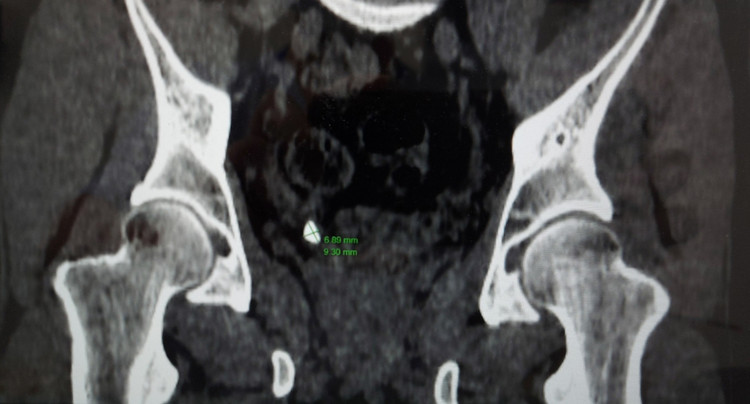

Ngay lập tức, người bệnh được các bác sĩ chỉ định làm các xét nghiệm, siêu âm bụng, chụp cắt lớp vi tính và xác định người bệnh bị sỏi niệu quản phải 1/3 dưới (nằm ở vị trí đoạn nối của niệu quản khi vào tới bàng quang), sỏi kích thước xấp xỉ 9x7mm.

|

| Sỏi thận trong cơ thể người bệnh trên phim chụp - Ảnh BVCC |